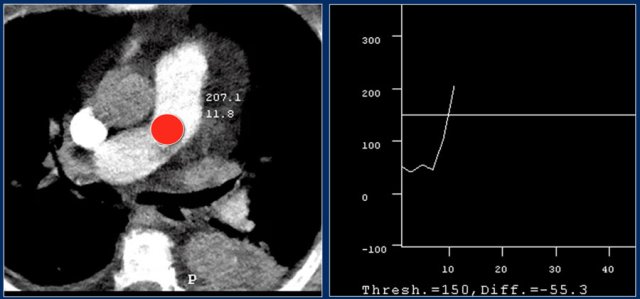

For good timing bolus tracking is needed.

A ROI is placed in the pulmonary trunk.

When the treshhold of 150 HU is reached, the patient is asked to breath in and scanning is started immediately.